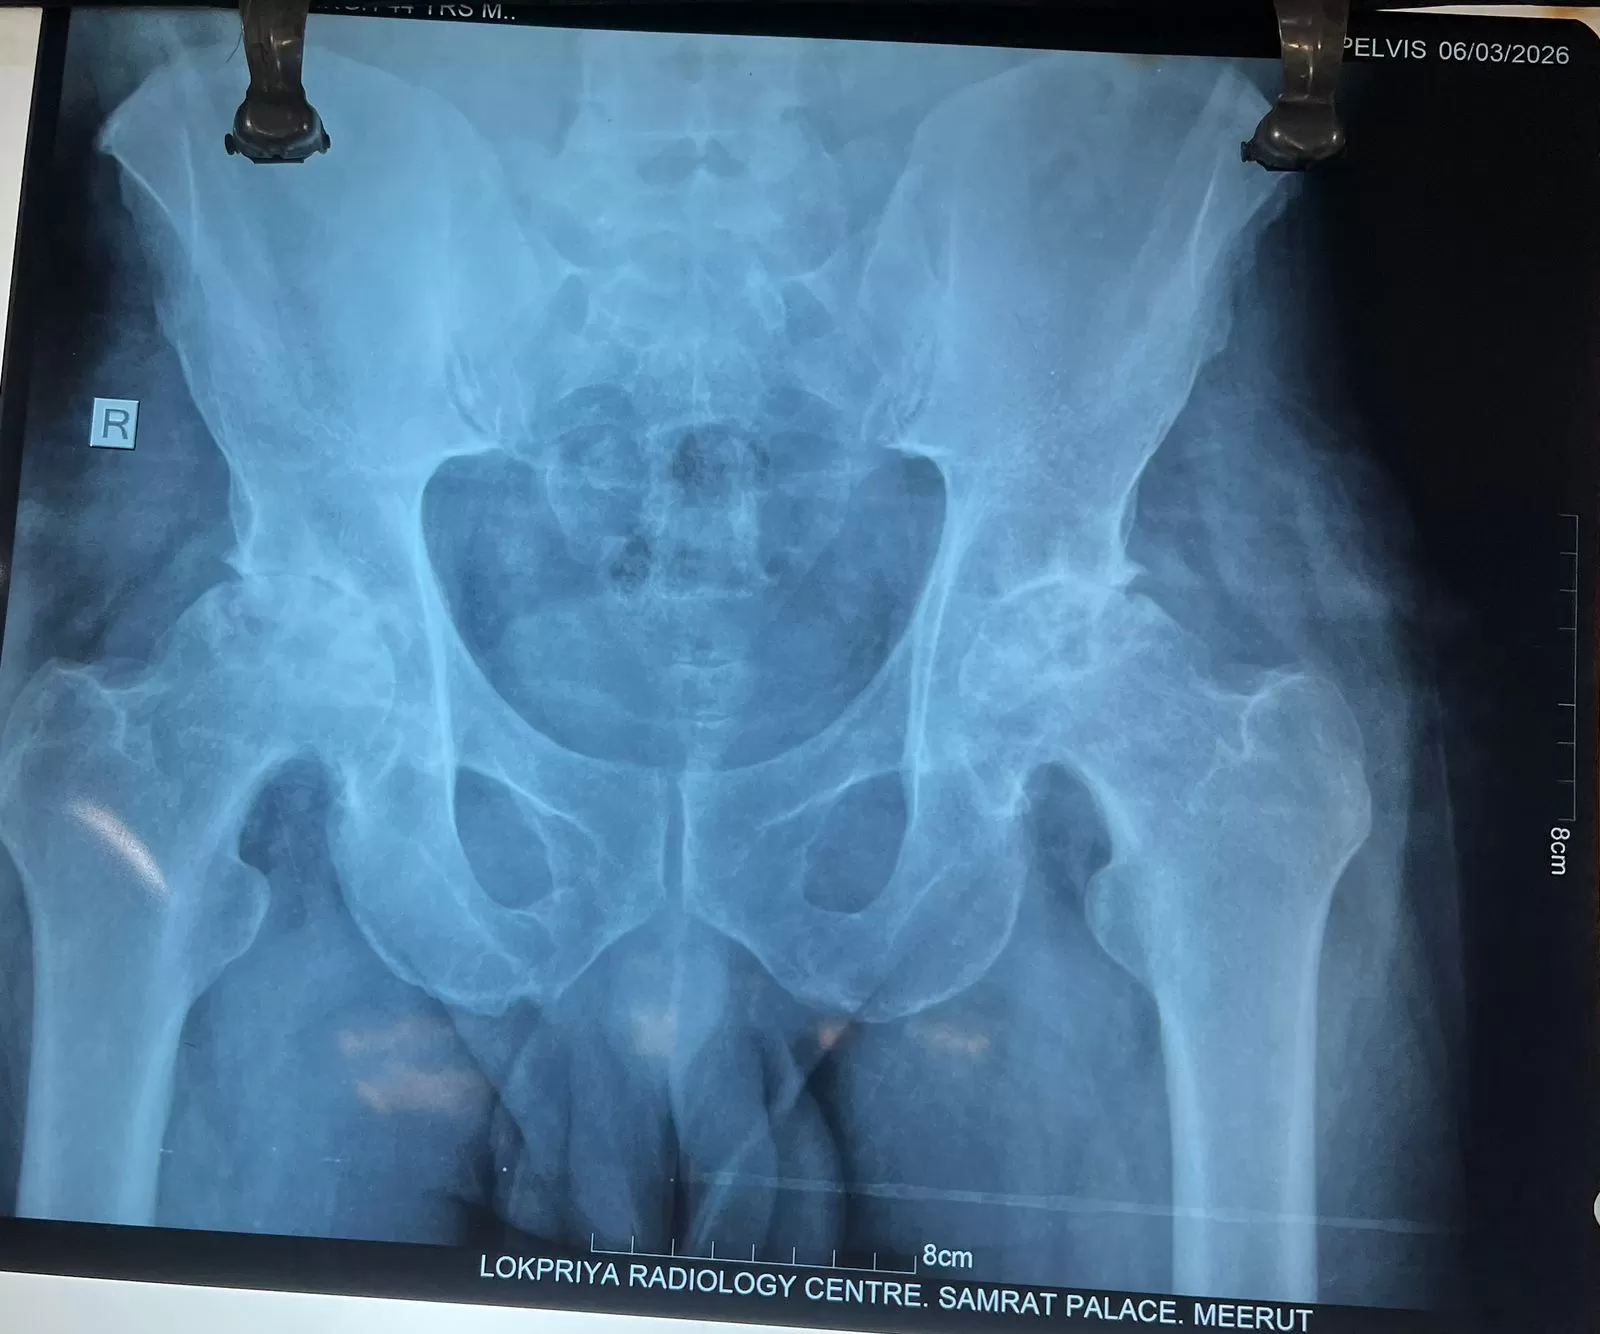

Prempal

Name: Prempal

Date of Operation: 24 March 2026

Age: 30/m Years